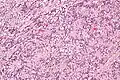

| Micrograph of an intranodal palisaded myofibroblastoma. H&E stain. | |

IPMs are diagnosed by examination of the tissue by a pathologist. They have a rim of peripheral lymphoid tissue (remnant of a lymph node) and consist of spindle cells with nuclear palisading. Red blood cell extravasation is common and blood vessels surrounded by collagen with (fine) peripheral spokes (amianthoid fibers) are usually seen.[2]

Immunostains for smooth muscle actin and cyclin D1 are characteristically positive. The main histologic differential diagnosis is schwannoma.